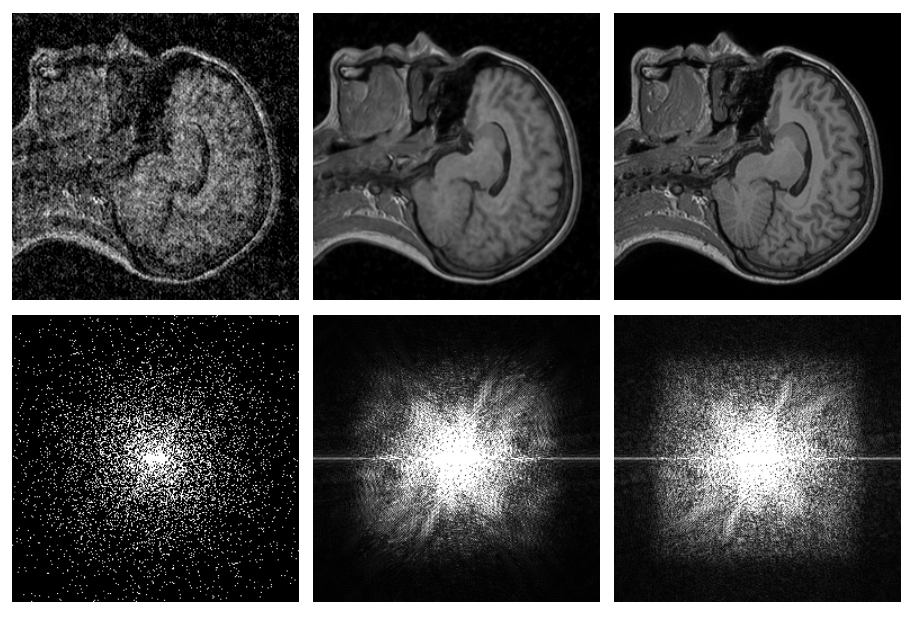

Projekt s názvom Noise2Noise AI má za úlohu skenovať fotky pomocou umelej inteligencie a následne ich opraviť na základe zaznamenaných údajov. Ako u každej umelej inteligencie, tak aj tento výskum zahŕňa akýsi „virtuálny tréning“. V tomto prípade bolo AI trénované na vyše 50 000 rôznych snímkach, ktoré majú dopomôcť v snahe doplniť chýbajúce alebo nekvalitné pixely do fotografií. Výskumníci uvádzajú, že systém dokáže odstrániť narušené zrnité prvky a nahradiť ich kvalitnými detailmi.

Využitím systému Noise2Noise vám už zrnité fotky nebudú vytvárať vrásky na čele.

Tento typ umelej inteligencie si určite hravo nájde využitie v praxi, čo sa môže týkať napríklad menej kvalitných fotoaparátov v mobilných telefónoch a tabletoch. Výskum však ukázal, že sa systém javí ako extra efektívny aj v prípade MRI skenovania alebo úpravy astronomických záberov. Na podobnom princípe funguje systém, za ktorým stojí firma Intel spolu s Illinioskou Univerzitou. Ten má za úlohu zvyšovať kvalitu a detaily záberov fotených za šera, čo sa neskôr firma chystá využiť pri zdokonaľovaní prostriedkov pre nočné videnie.